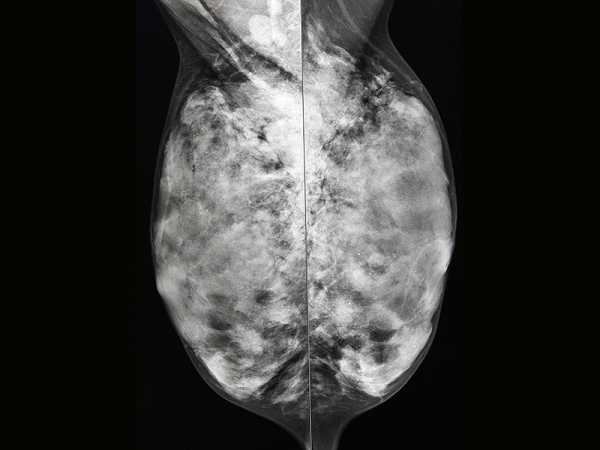

В современной медицине различают 2 вида мастопатии: узловую и диффузную. Для первого вида заболевания характерно образование плотных узлов размером до 25-30 мм. Что касается второго, то в этом случае образуются небольшие просовидные тяжи и узелки.

Диффузную форму патологии очень часто лечат при помощи наружных лекарственных средств. Однако следует отметить, что для проведения эффективной терапии местные мази, гели и кремы обязательно комбинируют с фитокомплексами, гормональными препаратами и витаминами.